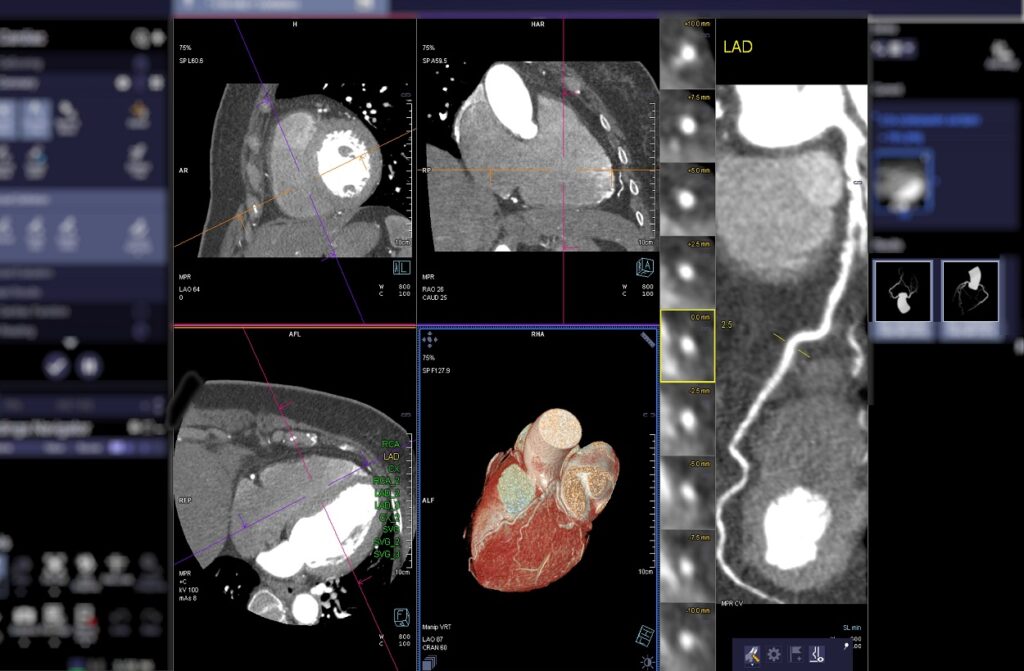

Coronary Artery CT Angiogram

This non-invasive imaging test uses computed tomography (CT) technology to visualize the coronary arteries.

How it happens: You’ll lie on a table that slides into a donut-shaped scanner. A contrast dye is injected into your arm through an IV line to highlight your blood vessels. The scanner rapidly takes multiple X-ray images from different angles, creating detailed 3D pictures of your heart and coronary arteries. The procedure typically takes less than 30 minutes.

When it’s necessary: This test may be recommended to evaluate chest pain, assess coronary artery disease risk, or check previously placed stents or bypass grafts.